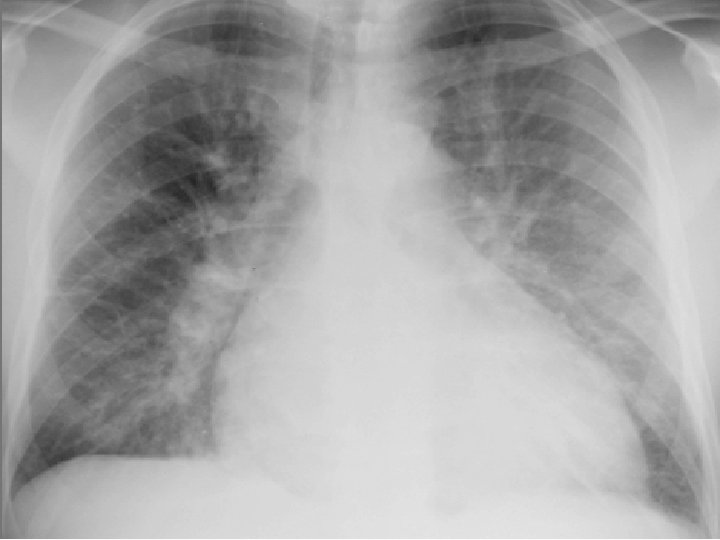

Insuficiencia C. Izquierda: • • Fatiga Intolerancia al ejercicio Nicturia Disnea de esfuerzos Palpitaciones, angina, síncope Extremidades frías Tos seca nocturna EDEMA AGUDO PULMONAR

Criterios de Framingham u MAYORES: Presión venosa central > 16 cm H 20 Reflujo hepato yugular Edema pulmonar agudo Disnea paroxística nocturna Ingurgitatión yugular Cardiomegalia Estertores S 3

Examen Físico del Tórax: • • • Desplazamiento apical por cardiomegalia doble levantamiento apical, frémito, etc. Precordio enérgico paraesternal (HAP) S 3 o galope ventricular, Soplos Derrames, estertores.